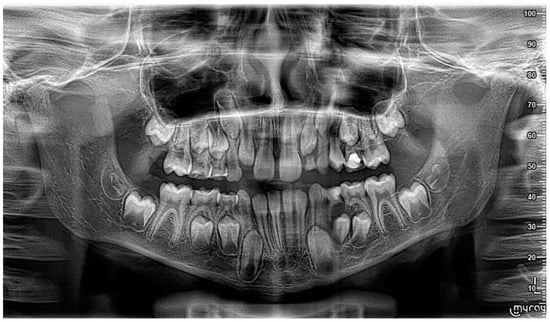

2. Case Report

3. Follow-Up and Outcomes